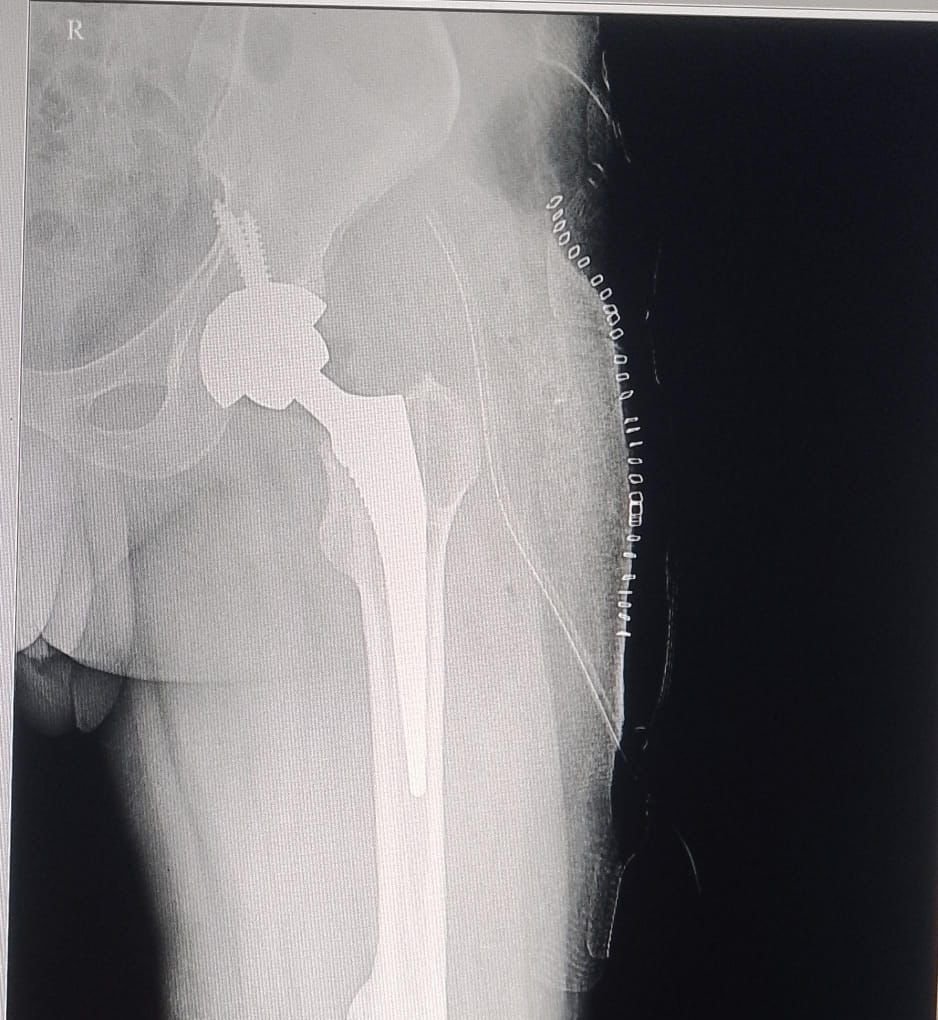

पत्थलगांव। जशपुर जिले के चिकित्सा इतिहास में एक महत्वपूर्ण उपलब्धि जुड़ गई है। पत्थलगांव स्थित श्री ए.जी. हॉस्पिटल ने पहली बार टोटल हिप रिप्लेसमेंट (THR) सर्जरी को सफलतापूर्वक संपन्न कर एक नया कीर्तिमान स्थापित किया है। यह जटिल और बड़ी सर्जिकल प्रक्रिया मानी जाती है, जिसमें क्षतिग्रस्त कूल्हे के जोड़ को हटाकर उसकी जगह कृत्रिम जोड़ (प्रोस्थेसिस) लगाया जाता है।

इस महत्वपूर्ण सर्जरी को श्री ए.जी. हॉस्पिटल की विशेषज्ञ डॉक्टरों की टीम ने सफलतापूर्वक अंजाम दिया। सर्जरी में डॉ. राहुल मिश्रा, डॉ. अजीत गुप्ता, डॉ. हेमंत भगत के साथ चिकित्सा स्टाफ जय प्रकाश भगत, आशीष बेक, प्रकाश और नरेंद्र ने महत्वपूर्ण भूमिका निभाई। टीम के सामूहिक प्रयास और आधुनिक तकनीक के उपयोग से यह जटिल ऑपरेशन पूरी तरह सफल रहा।चिकित्सकों ने बताया कि टोटल हिप रिप्लेसमेंट उन मरीजों के लिए अत्यंत लाभकारी सर्जरी है

जिनके कूल्हे के जोड़ गंभीर रूप से क्षतिग्रस्त हो जाते हैं या जिन्हें लंबे समय से असहनीय दर्द और चलने-फिरने में कठिनाई का सामना करना पड़ता है। सर्जरी के बाद मरीज सामान्य जीवन की ओर तेजी से लौट सकता है।श्री ए.जी. हॉस्पिटल में इससे पहले भी कई गंभीर बीमारियों और जटिल सर्जरी का सफलतापूर्वक उपचार किया जा चुका है।